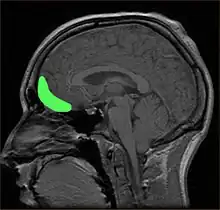

L'impulsivité est un comportement présent dans de nombreux troubles neuropsychiatriques incluant trouble du déficit de l'attention, trouble bipolaire, trouble du spectre de l'alcoolisation fœtale, trouble de la personnalité antisociale, trouble de la personnalité borderline et trouble de la personnalité histrionique et certaines causes de dépression et suicide[9],[10]. Des niveaux anormaux de traits impulsifs peuvent être causés par des maladies neurodégénératives, un traumatisme crânien, des infections virales ou bactériennes ou neurotoxicité à la suite de l'exposition de produits chimiques. Certains traumatismes ou anomalies du cortex orbitofrontal et le gyrus frontal inférieur provoquent les traits de l'impulsivité[11],[12],[13], bien que certaines connexions cérébrales peuvent contribuer à de différentes manifestations de l'impulsivité[14].